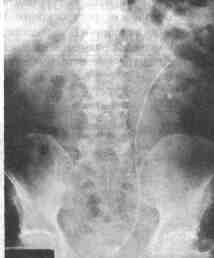

![]() Рис. 2-2. Обзорная урограмма. Определяется несмещающийся, самоудерживающийся мочеточниковый стент 13. Объясните разницу между мочеточниковым катетером и мочеточниковым